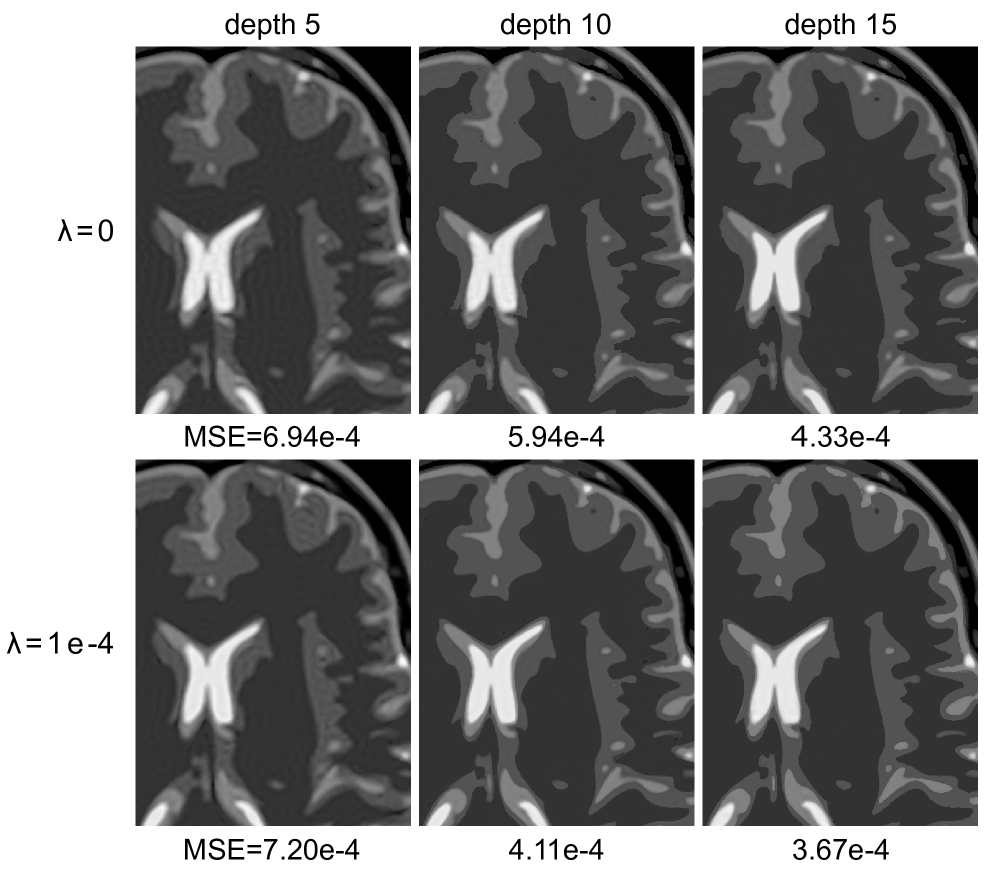

Though our theory focuses on depth 2 INRs (i.e., single hidden-layer), we also explore the effect of depth on the induced image domain with and without weight decay regularization. Using the same setup as previously used for the brain phantom, in Figure 6 we show the results of fitting an INR with depths of 5,105105,105 , 10, and 15151515. These results show that with or without weight decay regularization, increasing INR depth results in lower image domain MSE and fewer ringing artifacts, indicating that deeper INRs may be biased towards piecewise constant (or piecewise smooth) reconstructions. Additionally, a comparison of the reconstructions in the first and second rows of Figure 6 demonstrates that training deep INR with weight decay regularization gives lower image domain MSE and visually improved reconstructions, showing that weight decay regularization can have benefits for recovery with deep INR networks, as well.

Refer to caption

Figure 6: Effect of INR depth on image recovery. Top row: reconstructions using no regularization (λ=0)𝜆0(\lambda=0)( italic_λ = 0 ). Bottom row: reconstructions using standard weight decay regularization (λ=1e-4(\lambda=\text{1e-4}( italic_λ = 1e-4). Increasing the INR depth leads to lower image domain MSE and less visible ringing artifacts and sharp edges. Additionally, for each depth, a visible improvement in the quality of reconstructions is observed when using weight decay regularization.